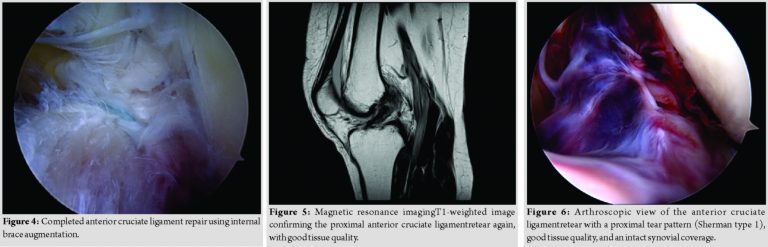

A 47-year-old athletic female patient (165cm; 63kg) was referred to our trauma department by ambulance after she fell twisting her left knee while downhill skiing at high speed. Clinical examination revealed a moderate effusion of the left knee with a positive Lachman, Drawer, and pivot shift test. Radiographic examination showed regular bony configuration of the left knee with no associated fractures while magnetic resonance imaging (MRI) confirmed a proximal ACL tear with no evidence of concomitant chondral/ meniscal/ ligamentous injuries (Fig. 1). The patient underwent a knee arthroscopy on the same day where the radiological findings were confirmed. The ACL tear presented with a proximal tear pattern (Sherman type 1), good tissue quality, and an intact synovial coverage so that an arthroscopic ACL repair using internal brace augmentation was performed (see surgical technique below, Fig. 2, 3, 4). Postoperatively, the left knee was immobilized in a neoprene splint for 2 days only with full weight-bearing as tolerated on crutches for 6 weeks. Passive mobilization of the knee started immediately on the 1stpost-operative day followed by increasing active and assistive mobilization. Knee flexion was limited to 90 degrees for 4 weeks. Physiotherapy (3 times a week) and aquatic therapy (once a week) completed the post-operative care. The patient was discharged in good general condition with a total inpatient stay of 2 days. The 6-week follow-up assessment showed negative Lachman and pivot shift tests, a 1.0mm side-to-side laxity (left side: 6mm, right side 5mm) measured with the KT-1000 arthrometer (MED metric Corp; San Diego, USA) and a restricted knee flexion of 100 degrees while 6-monthfollow-up assessment demonstrated a considerably improved range of movement with 120 degrees of knee flexion. At 1-year follow-up assessment, the pain-and complaint-free patient demonstrated a full range of knee motion and no signs of instability were observed. The patient started with running and cycling exercises 8-week postoperatively and returned to alpine skiing 3 months postoperatively. However, just 1 week after, her 1-year follow-up visit, the patient experienced another severe ski fall with twisting of the left knee and an immediate audible popping noise. A large hemarthrosis developed and patient clinically demonstrated with a positive Lachman, Drawer, and pivot shift test. Consequently, an MRI scan confirmed the diagnosis of a proximal ACL retear (Fig. 5). The patient underwent emergent knee arthroscopy – just 5 h after injury. Intraoperatively, the ACL retear presented with a replicated proximal tearpattern (Sherman type 1), good tissue quality, and an intact synovial coverage so that an arthroscopic ACL re-repair using internal brace augmentation was performed (Fig. 6, 7, 8). Again, the patient was very motivated and compliant with physiotherapy returning to sports 10-week post-injury and alpine skiing 3 months postoperatively. The patient demonstrated a full range of knee motion and negative instability tests with a 1.0mm side-to-side laxity difference (left side: 6mm, right side 5mm) at 6-and 12-month follow-up, respectively. The subjective outcome parameters remained good at 12-month follow-up with the International Knee Documentation Committee score of 83, Lysholm score of 95, and a pre-and post-operative Tegner score of 7. MRI at 12-month follow-up confirmed the integrity of the repaired ACL (Fig. 9).

A hemarthrosis was drained on insertion of the arthroscopic cannula in both cases. Using the two standard anterolateral and anteromedial portals, an arthroscopic washout as well as a diagnostic arthroscopy were performed confirming the radiographically suspected findings with a hook probe. The ACL was carefully assessed, including tear pattern, tissue quality, and synovial coverage of the ACL remnant: Aproximal ACL tear (Sherman Type 1) with good tissue quality and an intact synovial coverage as well as no concomitant osteochondral lesions nor meniscal injuries were present in both arthroscopies (Fig. 2 and 6).

An ACL repair utilizing an internal brace augmentation was performed in both cases as popularized by van der List and DiFelice [5]: Using a labral scorpion suture passer (Arthrex; Naples, USA), a No. 2 Fiber Wire® (Arthrex; Naples, USA) was passed 3 times through the ACL remnant – approximately 1cm distal to the ACL tear (Fig. 3 and 7). The femoral tunnel was drilled in an anatomic manner at the femoral footprint with 130degrees knee flexion using a spade tip drill pin (Arthrex; Naples, USA) and a shuttling loop was subsequently passed through the femoral tunnel. The tibial drilling guide (Smith and Nephew, London, United Kingdom) was then placed at the anterior center of the ACL tibial footprint and the tibial tunnel was drilled through a small skin incision on the anteromedial aspect of the tibia. A shuttling loop was passed through the tibial tunnel. A suture retriever (Arthrex; Naples, USA) was placed through the anteromedial portal retrieving the tibial shuttling loop. The femoral shuttling loop as well as the Fiber Wire® suture were then placed into the tibial shuttling loop and passed through the tibial tunnel. Using the femoral and tibial shuttling loop, the Internal Brace construct consisting of a Tight Rope®(Arthrex; Naples, USA) armed with a Fiber Tape®(Arthrex; Naples, USA) and the Fiber Wire® suture was carefully shuttled through the tibia and femur so that the Tight Rope® button flipped at the femoral cortex (Figs. 4 and 8).